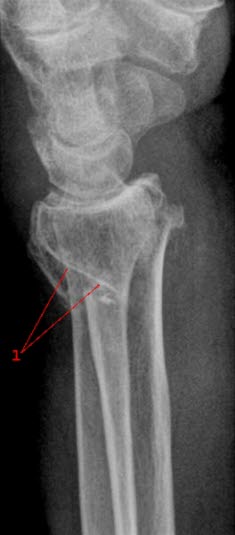

Det er som regel ønskelig at det blir tatt to røntgenbilder fra ulike retninger, vanligvis i rett vinkel på hverandre (se bilde forfra og fra siden). Er bildene tvetydige, eller det er et misforhold mellom det man finner ved legeundersøkelsen og røntgenfunnene, vurderes det å ta flere bilder også i andre retninger. Av og til tar man bilde av den andre siden for å kunne sammenligne.

Ved visse typer skader er det ønskelig å ta såkalte funksjonsbilder, det vil si bilder tatt med leddet i bestemte posisjoner. Slike bilder tas vanligvis ikke i den akutte fasen da smertene vil hindre bevegelsene. Visse typer ankelskader krever f.eks. at man må presse litt på ankelleddet for å få frem forandringer. Nakken må noen ganger avbildes både i fremoverbøyd og bakoverbøyd stilling.